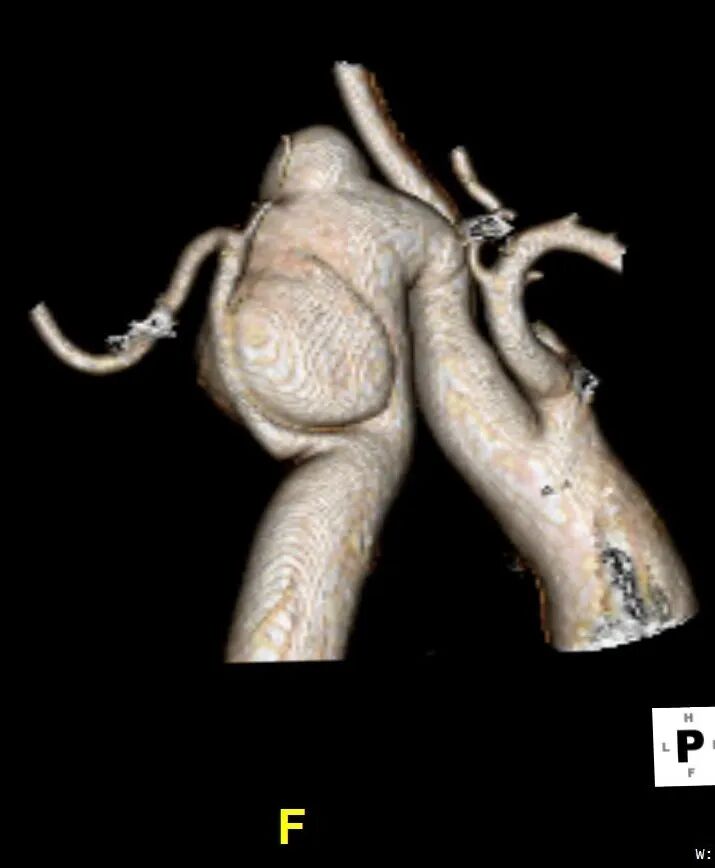

CTA检查

1、Ⅲ型弓,主动脉弓部远心端可见夹层动脉瘤,瘤体44mm*79mm,左锁骨下动脉发自瘤体下方降主段,且萎缩狭窄。

2、右椎动脉绝对优势,左椎动脉萎缩狭窄。